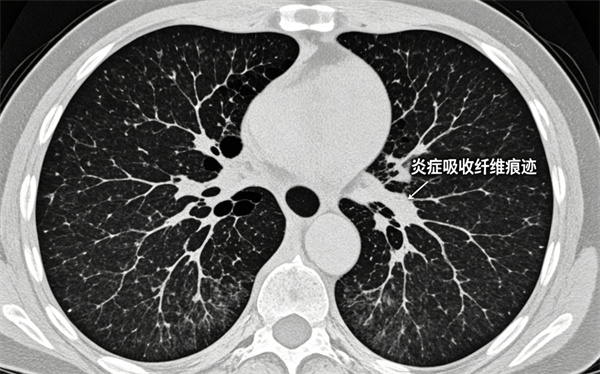

4条索影 斑片影

肺部炎症吸收后留下的纤维痕迹,属于良性陈旧性改变。

无不适症状者,通常不影响健康。